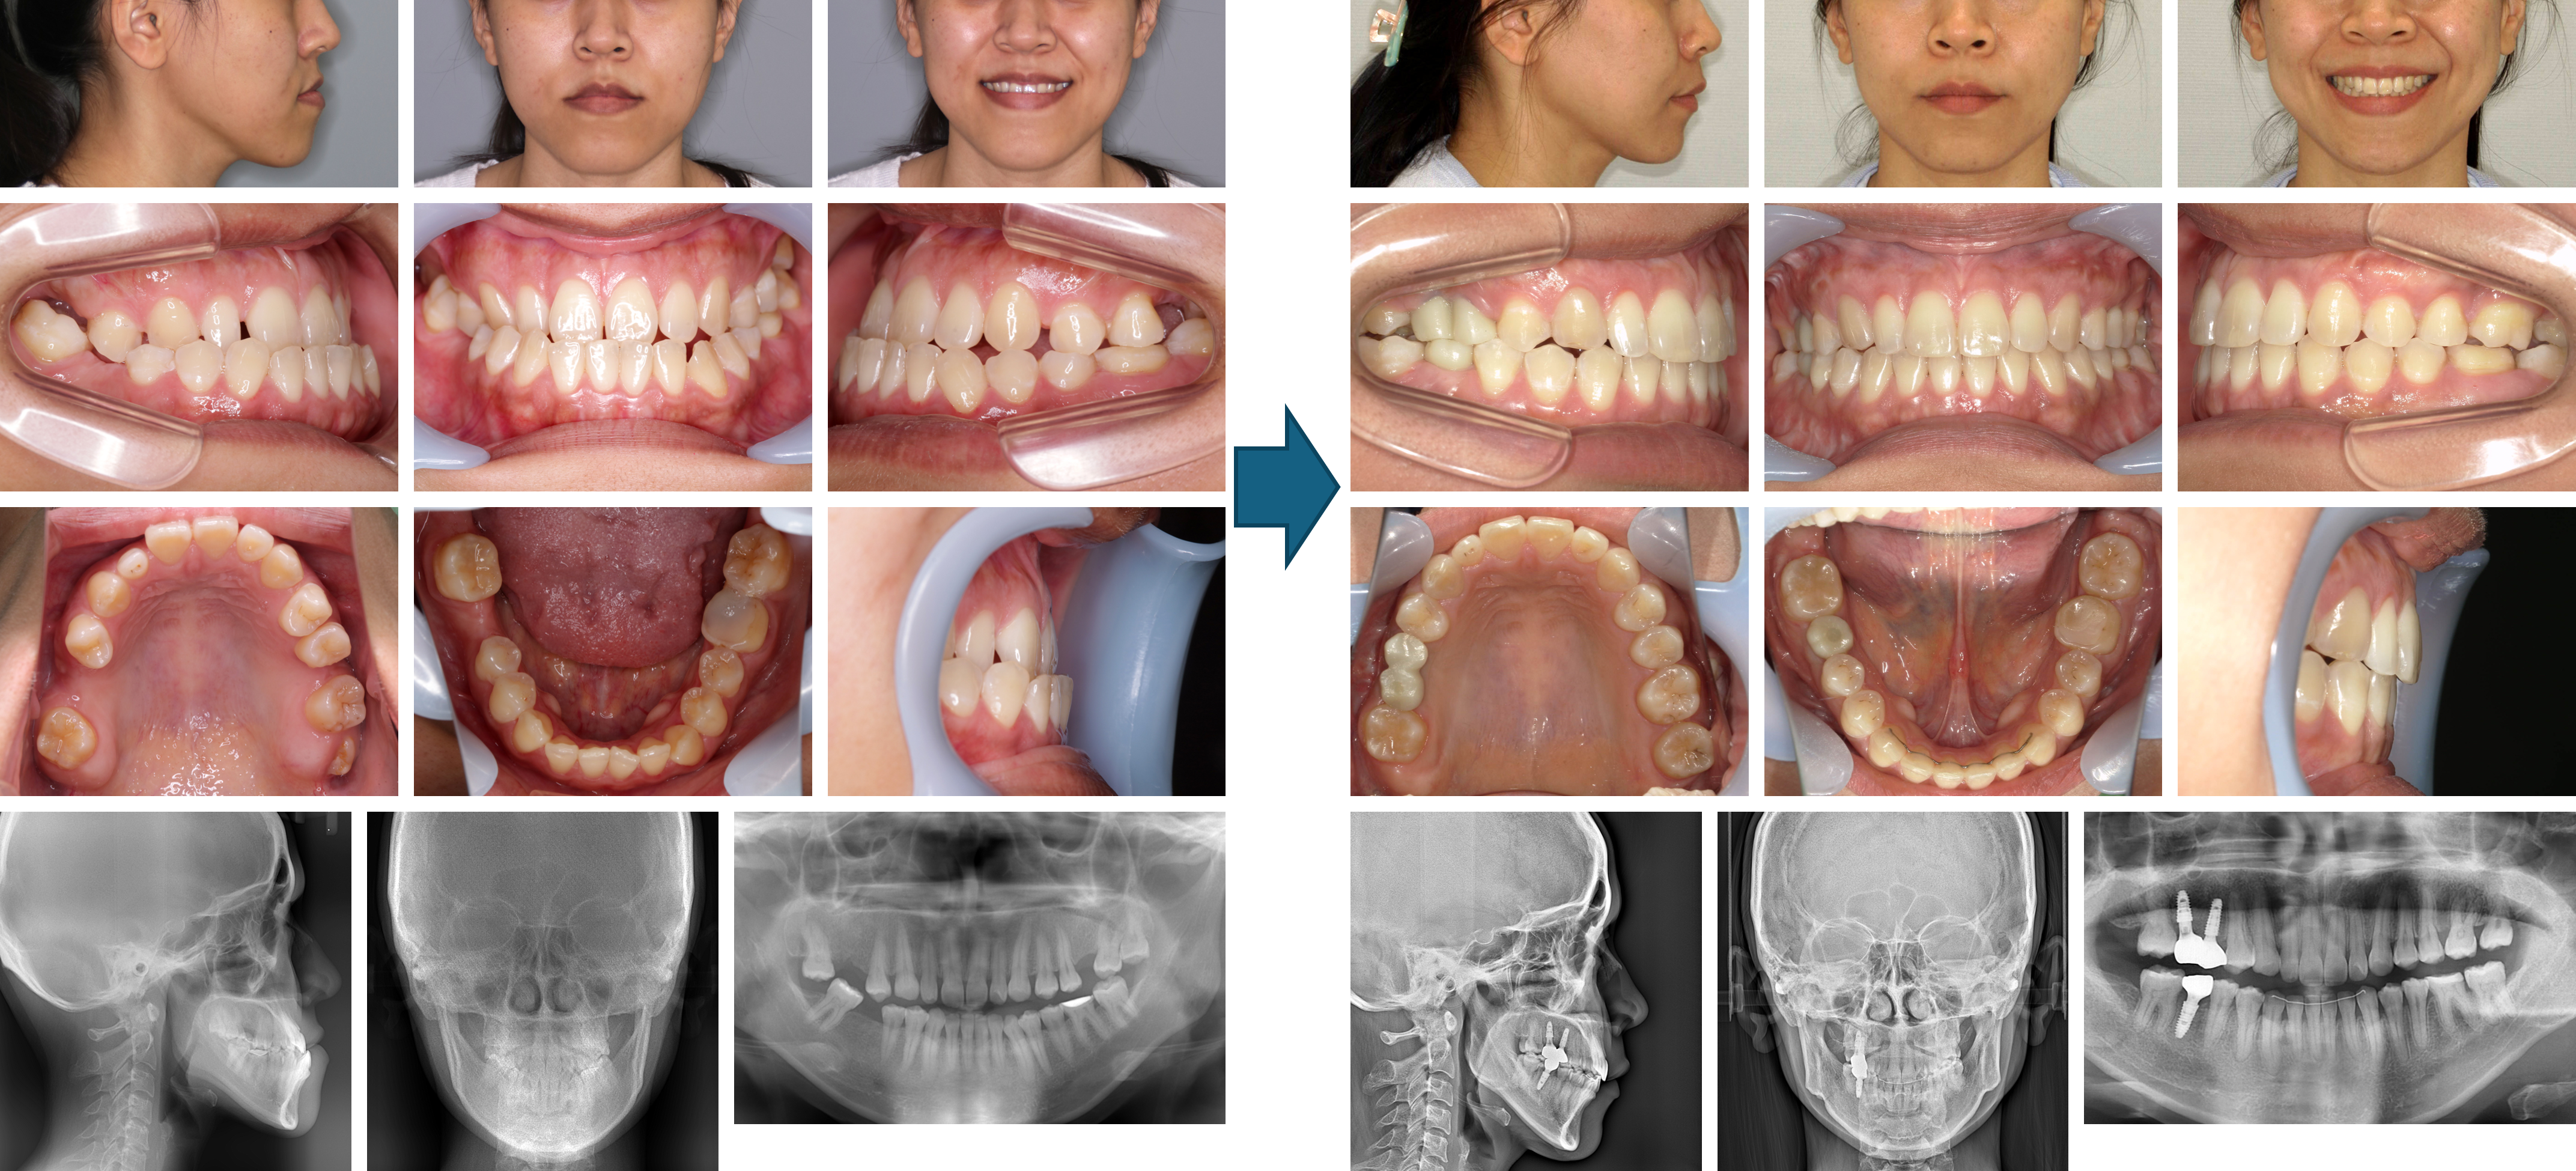

【治療例】初診時年齢:23歳8か月 / 性別:女性 / 主訴:前歯が出ているために口を閉じにくい

症例の概要:下唇が突出した受け口の側貌でした。顔貌の改善のために外科的矯正を選択しました。下顎歯列が内側に位置していたために下顎はバイヘリックス装置にて側方拡大し、それに合わせて上顎は急速拡大装置にて側方拡大を行い、上下顎非抜歯にて顎矯正手術を行いました。ただし、4本の第三大臼歯(親知らず)は手術のために抜歯を行いました。

主訴: 前歯が出ているために口を閉じにくい

診断名: 上下顎矯正手術を併用の下顎歯列の舌側傾斜を認める骨格性Ⅲ級、ハイアングル

使用した主な装置: マルチブラケット装置、急速拡大装置、顎間ゴム

抜歯/非抜歯および抜歯部位: 非抜歯

治療期間:4年6か月

治療回数:44回